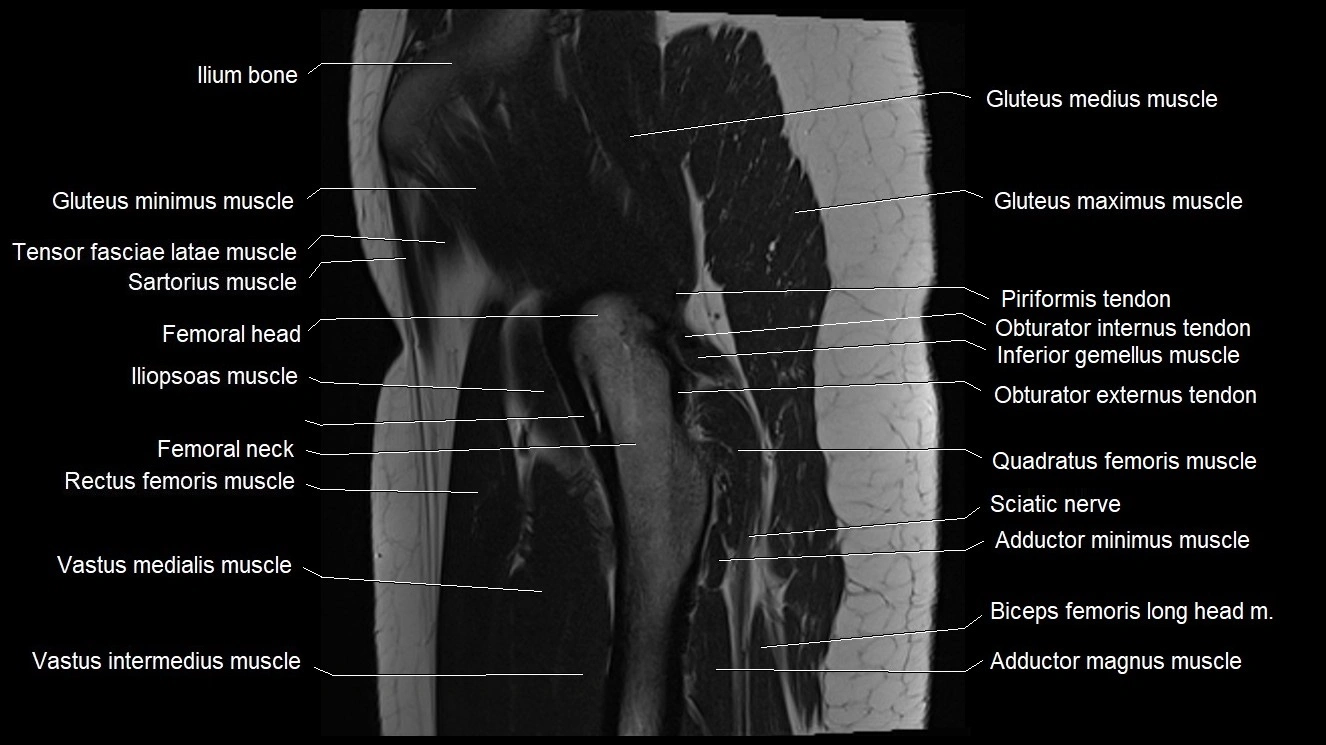

- Gluteus maximus muscle

- Gluteus medius muscle

- Gluteus minimus muscle

- Gluteus minimus tendon

- Iliopsoas muscle

- Inferior gemellus muscle

- Neck of femur

- Quadratus femoris muscle

- Rectus femoris muscle

- Sartorius muscle

- Tensor fasciae latae muscle

- Vastus intermedius muscle

- Vastus medialis muscle